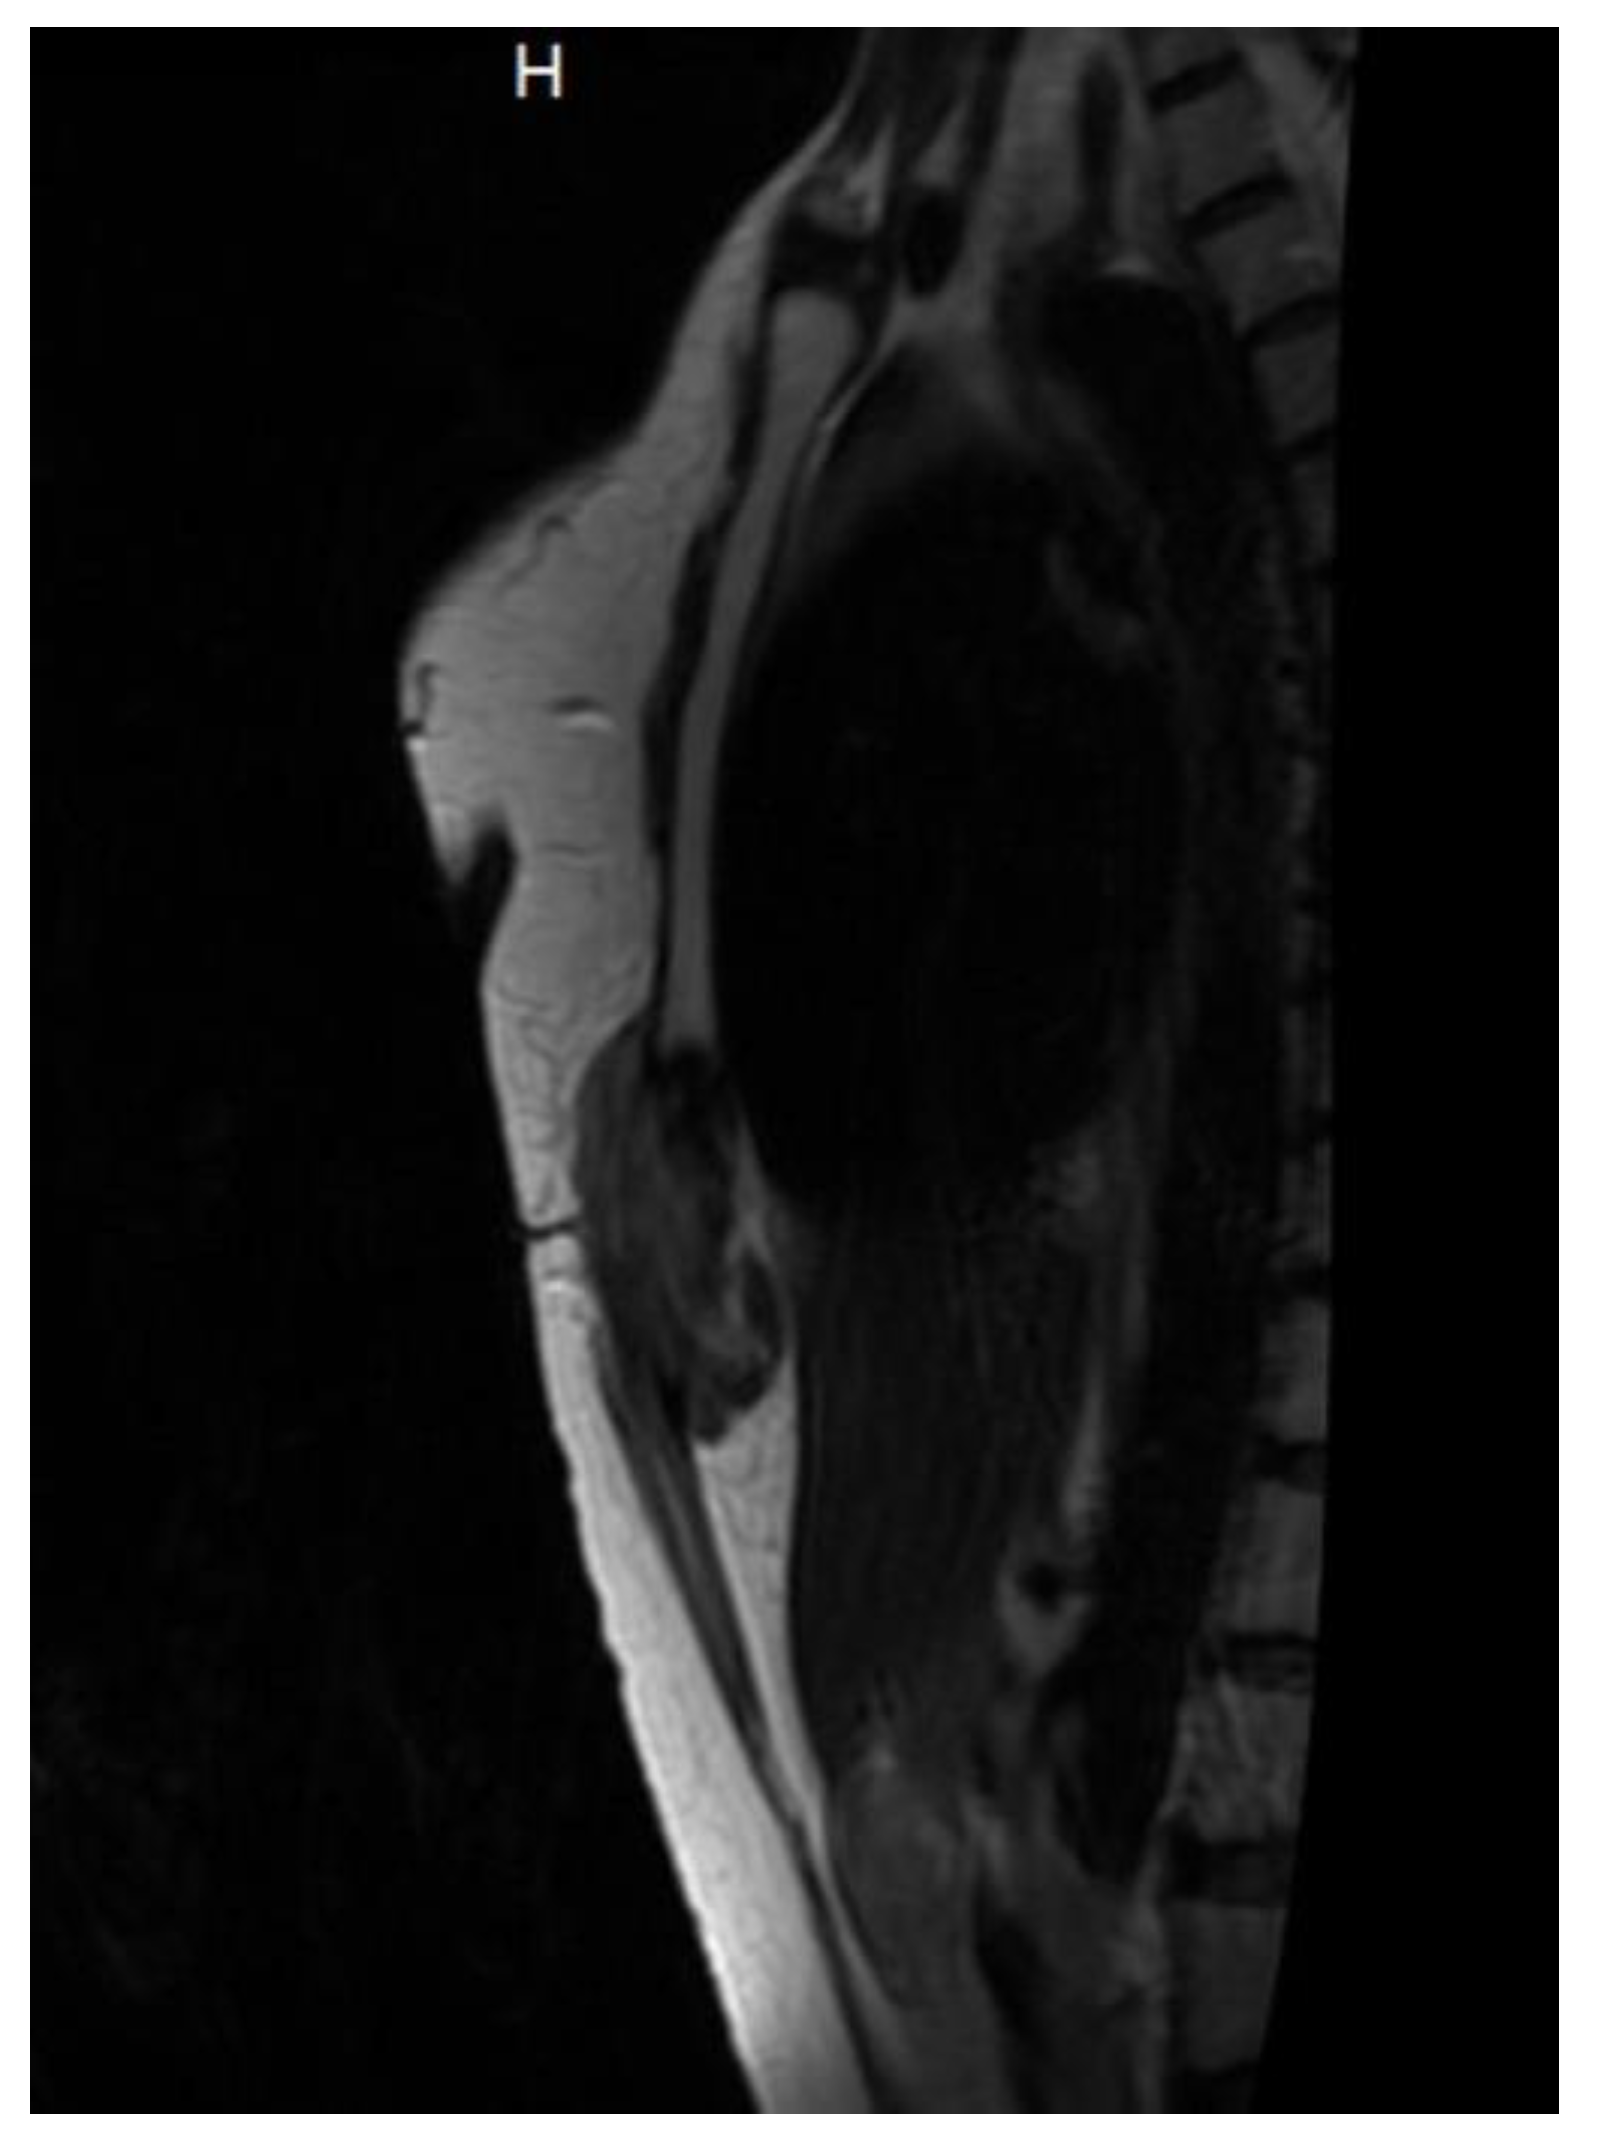

In April 2024, a thoracic MRI confirmed tumor recurrence at the same location, reinforcing the chronic, recurrent nature of the disease. (Figure 7)

Figure 7. MRI imaging of desmoid tumor with intrathoracic localization.